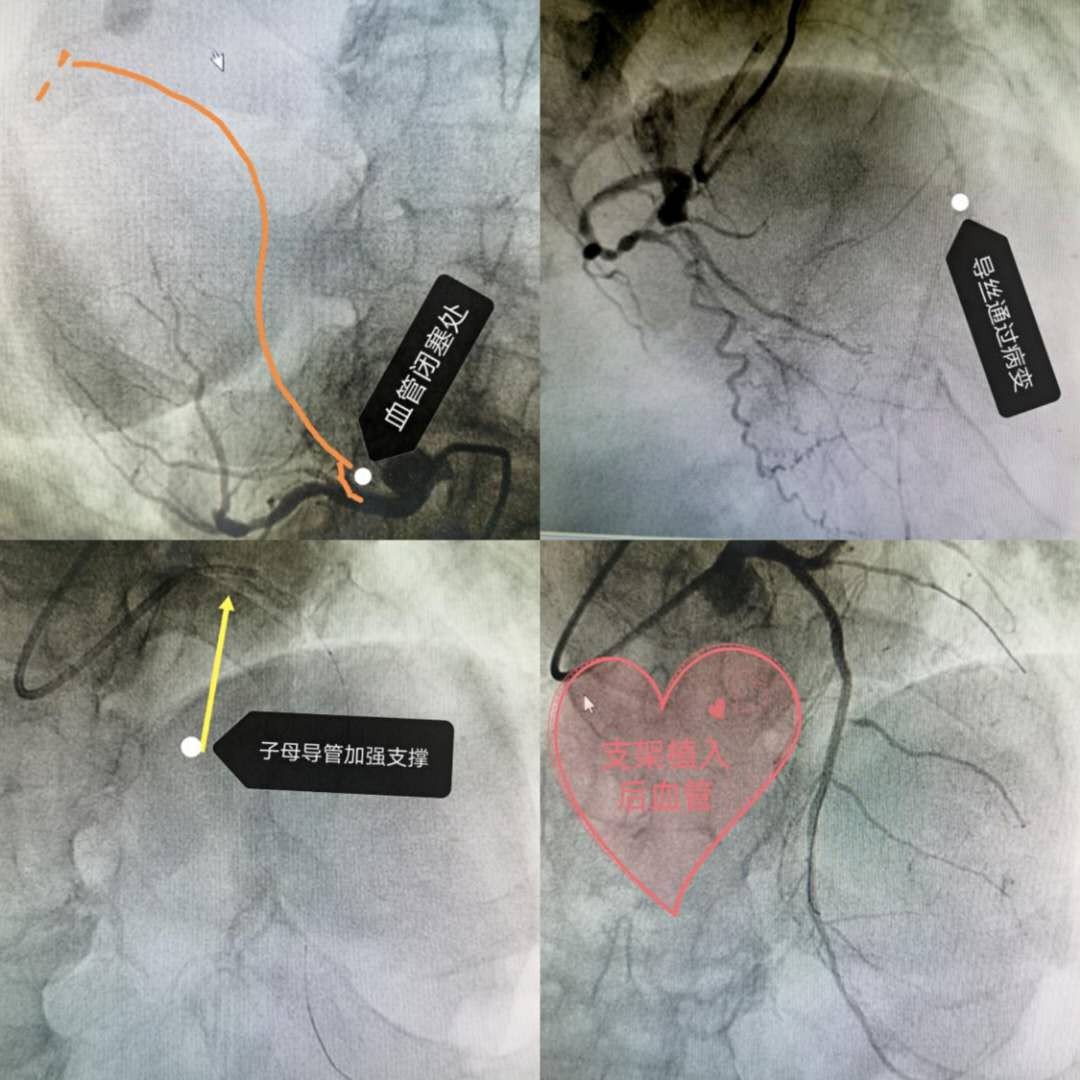

82歲退休教師,一位老先生,一周前急性前壁非ST抬高心肌梗死后反復(fù)發(fā)作心絞痛及左心衰,外地醫(yī)院無(wú)法完成心臟介入轉(zhuǎn)至我院。在充分評(píng)估病情、考慮獲益和風(fēng)險(xiǎn)比、并和家屬充分溝通后,CCU團(tuán)隊(duì)毅然決定給予老先生行緊急介入手術(shù)治療。術(shù)中造影發(fā)現(xiàn)多支血管病變,其中前降支閉塞并重度鈣化,手術(shù)難度和風(fēng)險(xiǎn)均超大,反復(fù)通過(guò)多根導(dǎo)絲嘗試并在對(duì)側(cè)造影指引下通過(guò)閉塞,大家松一口氣,但后面手術(shù)卻更艱難,由于超級(jí)鈣化、球囊無(wú)法通過(guò)閉塞處行擴(kuò)張治療,最后在5F子母導(dǎo)管支持下最小的直徑1.0/1.2/1.5mm球囊抵住行局部爆破、斑塊松解,終于通過(guò)閉塞處完成擴(kuò)張及支架治療。術(shù)后患者未在發(fā)作一次心絞痛及左心衰,順利康復(fù)出院。老爺子拉著大夫的手說(shuō)感謝徐醫(yī)附院給了他二次生命。